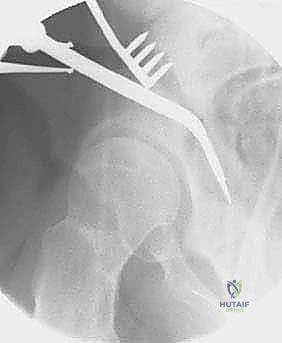

القطع الأول: القطع الإسكي غير المكتمل (Incomplete Ischial Osteotomy)

باستخدام إزميل خاص ذو زاوية (Angled Osteotome)، يتم إجراء قطع في عظم الإسك أسفل الحُق مباشرة (في الأخدود تحت الحُقي). يتم هذا القطع بتوجيه الأشعة السينية (Fluoroscopy) لضمان عدم اختراق المفصل. يحرص الدكتور هطيف على إبعاد العصب الوركي والأوعية السدادية بأمان تام.